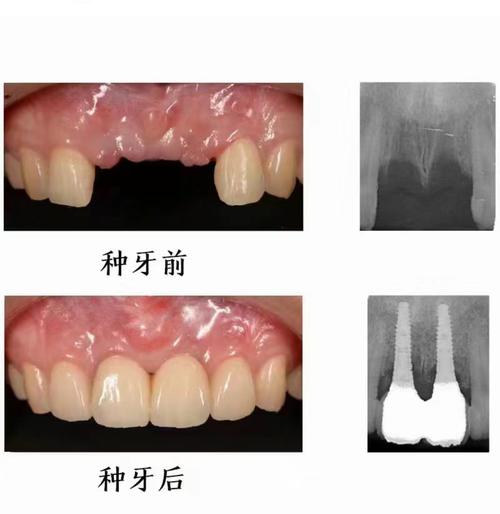

牙周炎是口腔常见的慢性感染性疾病,主要表现为牙龈炎症、牙周袋形成、牙槽骨吸收,最终导致牙齿松动脱落,下门牙作为口腔前牙区的核心牙齿,不仅承担着切割食物的功能,还对发音和面部美观至关重要,当牙周炎导致下门牙缺失后,种植牙因其良好的功能和美观效果,成为理想的修复方式,但牙周炎患者的种牙过程相对复杂,需严格把控治疗各环节,以确保种植体长期稳定。

- 牙冠修复:取模制作全瓷牙冠(颜色、形态匹配邻牙),试戴调整咬合后粘固,牙冠可选择氧化锆全瓷冠,强度高、美观性好,且生物相容性佳。